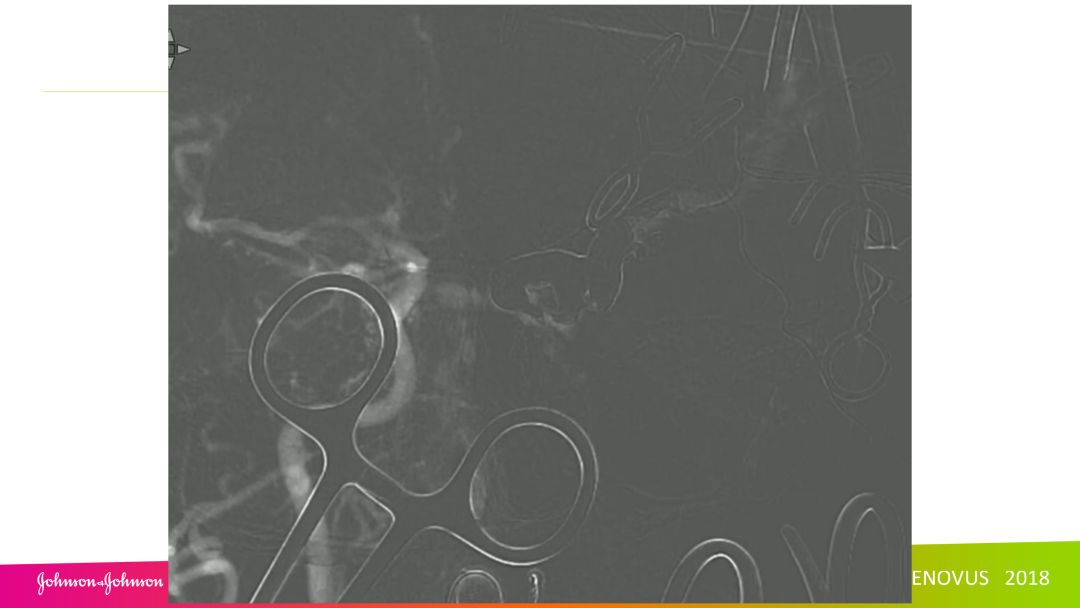

复合手术治疗海绵窦区硬脑膜动静脉瘘一例